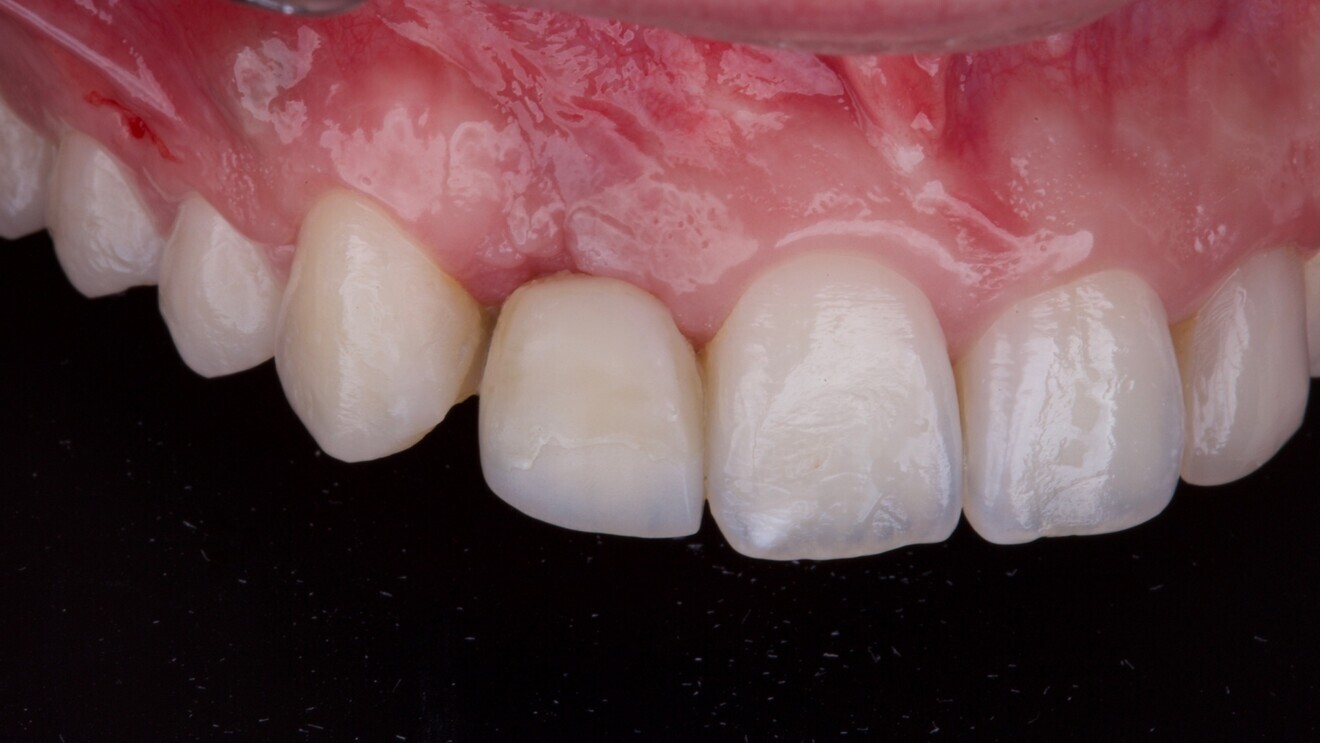

Fig. 4: Vertical guided bone regeneration procedure carried out after an eight-week healing period by experienced operators.

A provisional Maryland bridge was bonded to restore the edentulous area aesthetically. After an eight-week healing period, a vertical GBR procedure was performed by two experienced clinicians (MT and SMM). Antibiotic prophylaxis was administered (amoxicillin 2 g 1 hour preoperatively, followed by 1 g twice daily for eight days). The patient also rinsed with 0.2% chlorhexidine for 1 minute before surgery, and the surgical site was isolated with a sterile drape.

Anaesthesia was delivered using 4% articaine with 1:100,000 adrenaline (Ubistesin, 3M ESPE). A crestal incision through the keratinised mucosa was made using a No.15c blade, and a full-thickness flap was elevated. Vertical releasing incisions were placed two teeth away, both mesially and distally (Fig. 4).

The recipient site was debrided, and autogenous cortical bone was harvested from the ipsilateral mandibular ramus (external oblique ridge) using a bone scraper (MICROSS, META). A resorbable collagen membrane (OssMem Hard, Osstem Implant) was secured on the palatal aspect of the defect. A one-to-one mixture of autogenous bone and anorganic bovine bone (A-Oss; particle size: 0.25–1.00 mm; 0.5 g in total; Osstem Implant) was packed into the defect. The membrane was then stabilised with two additional fixation screws.